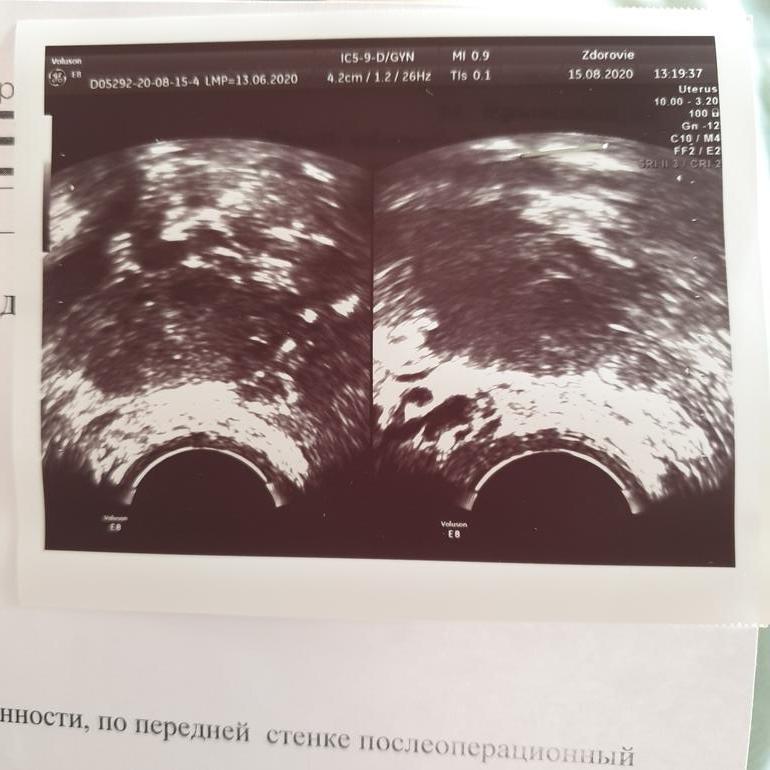

А вот фото и заключение сегодня:

Кристина, да по узи у вас овуляции не было в этом цикле, во-первых была бы жидкость в позадиматочном пространстве, и фолликул бы не исчез , а было бы либо желтое тело ,либо он был бы с рваными краями, а тесты они не показывают есть ли овуляция или нет. Тест только для того чтобы отследить ,когда она может наступить , то есть пик выброса ЛГ лютенизирующего гормона, а он происходит и тогда ,когда овуляции по факту может и не быть , ну я думаю вы поняли про что я. Тесты не информативные к сожалению и не дают 100% гарантии об овуляции. Я вам для примера прикреплю мое узи , на след день после овуляции